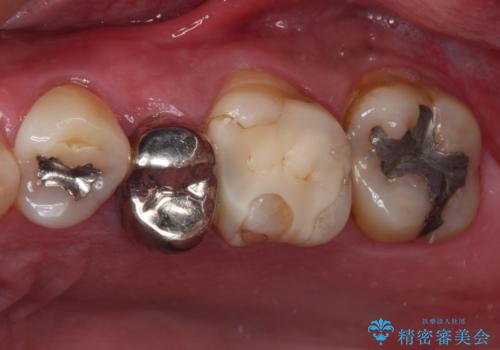

- 奥歯の詰め物が外れてしまったとのことで来院された患者様です。

レントゲン写真より、既に根管治療がされている歯であり、根尖部に骨透過像が認められました。

根管治療の際に、咬み合う上顎の銀歯が内側に入り込んでいることも気になるとのことであったため、部分矯正を行い、その後上下を同時に補綴治療することとしました。